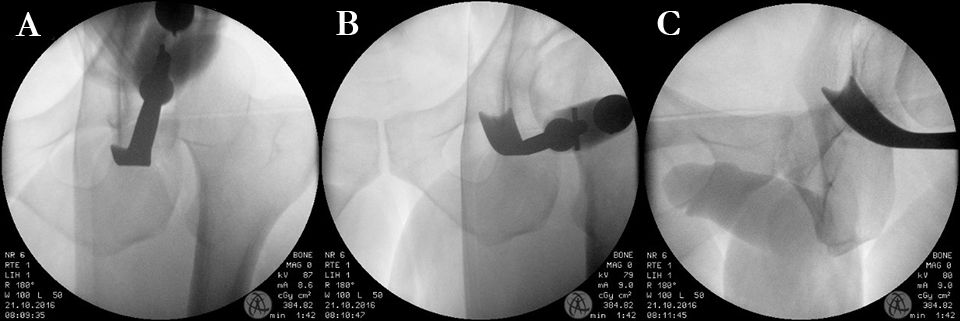

The incomplete ischium osteotomy, preserving the posterior half of the posterior acetabular column, is performed under radiological control with a curved 15mm osteotome. The osteotomy is initiated at the infracotyloid groove, which can be palpated very clearly with the tip of the osteotome, and ascends toward the spina ischadica (Fig. 7). At this point of the operation the surgeon needs to be aware of the anatomical proximity of the sciatic nerve, avoid Intraarticular penetration with the osteotome and guard against transection of the posterior column (Fig. 7, 8). To reduce the risk of nerve injury, the hip is flexed and abducted for the osteotomy of the medial ischium (Fig. 9). For the osteotomy of the lateral ischium the leg is extended and externally rotated.

After the incomplete ischium osteotomy, the exposure of the pubis is performed using two blunt retractors placed around the pubis. Next the periosteum is carefully peeled from the bone and Hohmann retractors are placed under the periost around the pubic ramus to protect the neurovascular obturator bundle during the complete osteotomy of the pubis. The pubic osteotomy is performed medial of the pubic eminence in a sagittal angel of 30° under radiographic control using an oscillating saw first and a 15 mm chisel second (Fig. 10).

To avoid postoperative limitation in ROM or femoroacetabular impingement the freedom of motion after reorientation and before definite fixation of the acetabular fragment should be checked with minimum of 120° flexion and 30° internal rotation in 90° hip flexion. If an optimal acetabular reorientation and adequate ROM has been achieved the acetabular fragment is definitely fixed with four 4,5mm screws. The screw placement is verified with fluoroscopy to verify their extraarticular position (Fig. 16).